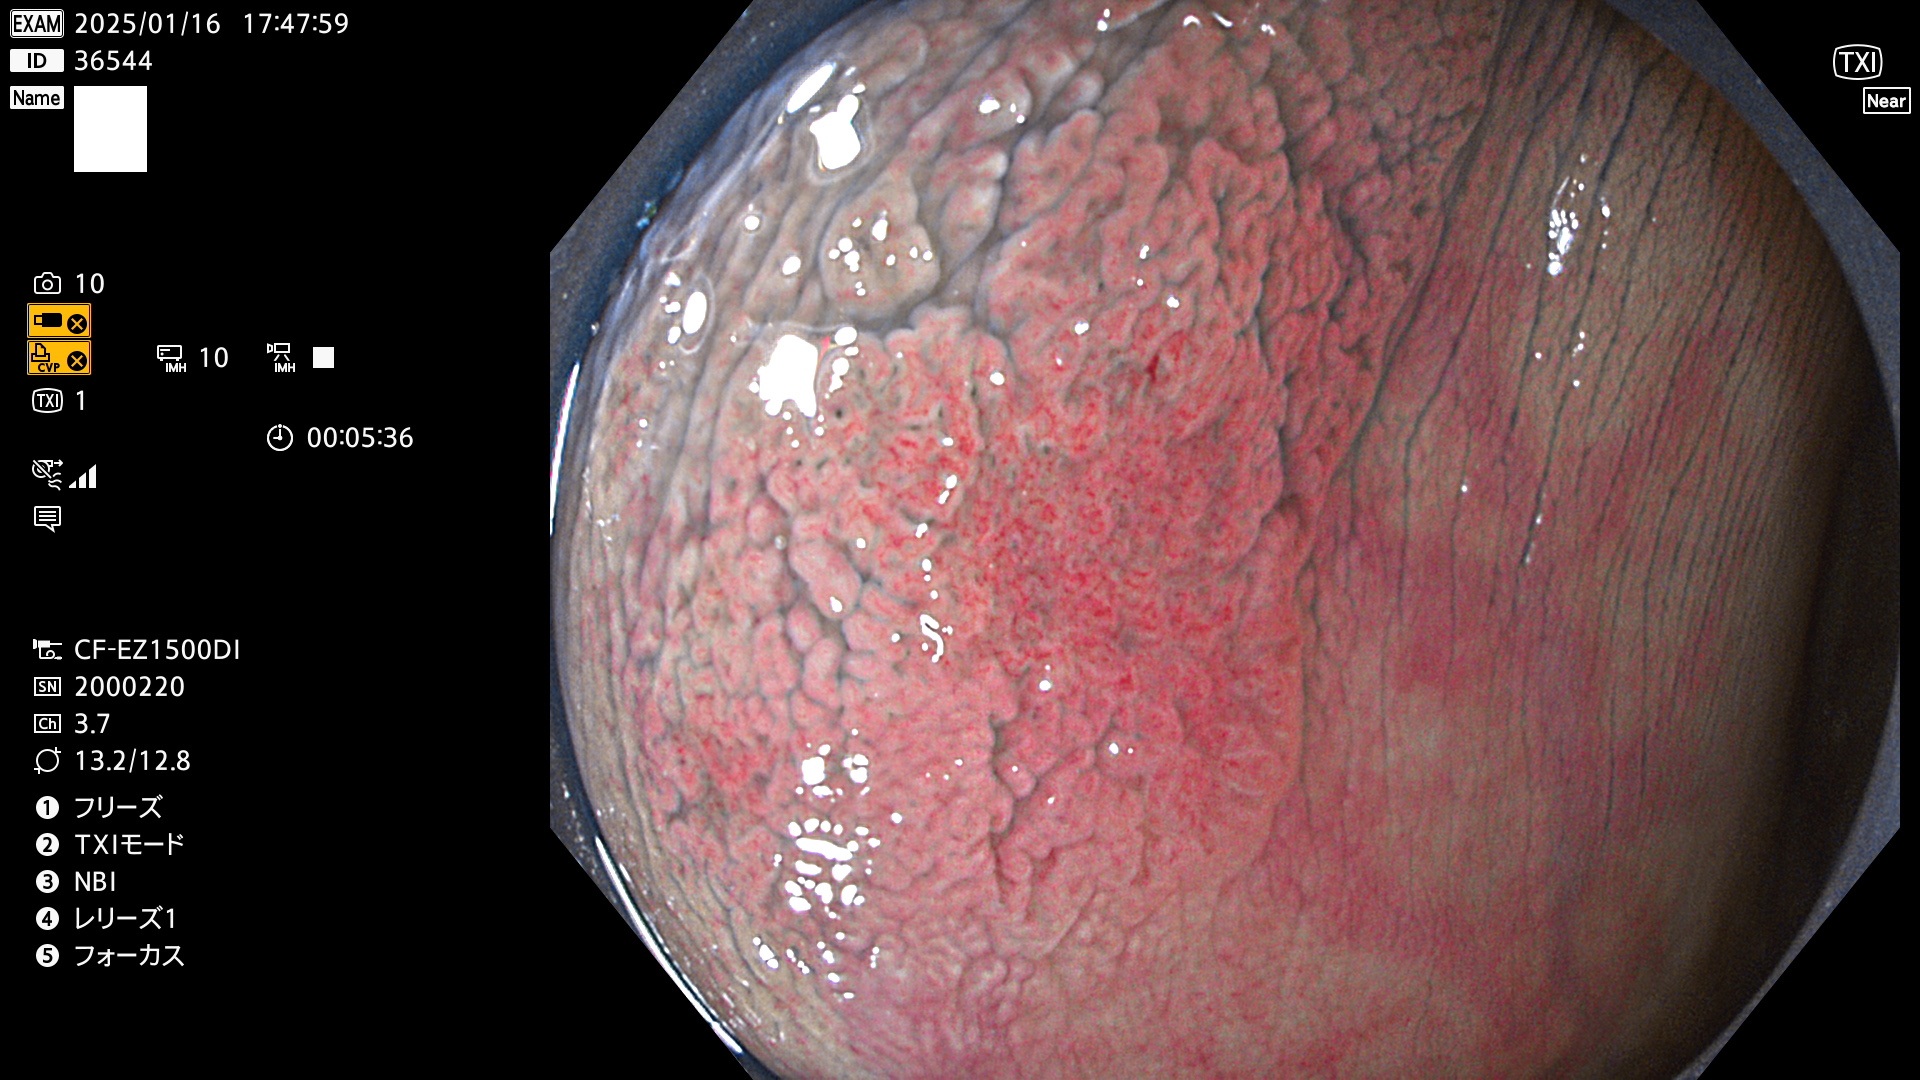

完全に平坦な物をUb、陥凹している物をUcと呼びます。最も発見が難しく危険な病変です。

毎週の検査(木・金・土・日)に発見されたUb、Uc型・腺腫を、その週の日曜の夜にUPし1週間、提示します。

抽出の対象期間 2025年1月16日〜1月19日の4日間(45件の検査)8個 (8/45=17%)